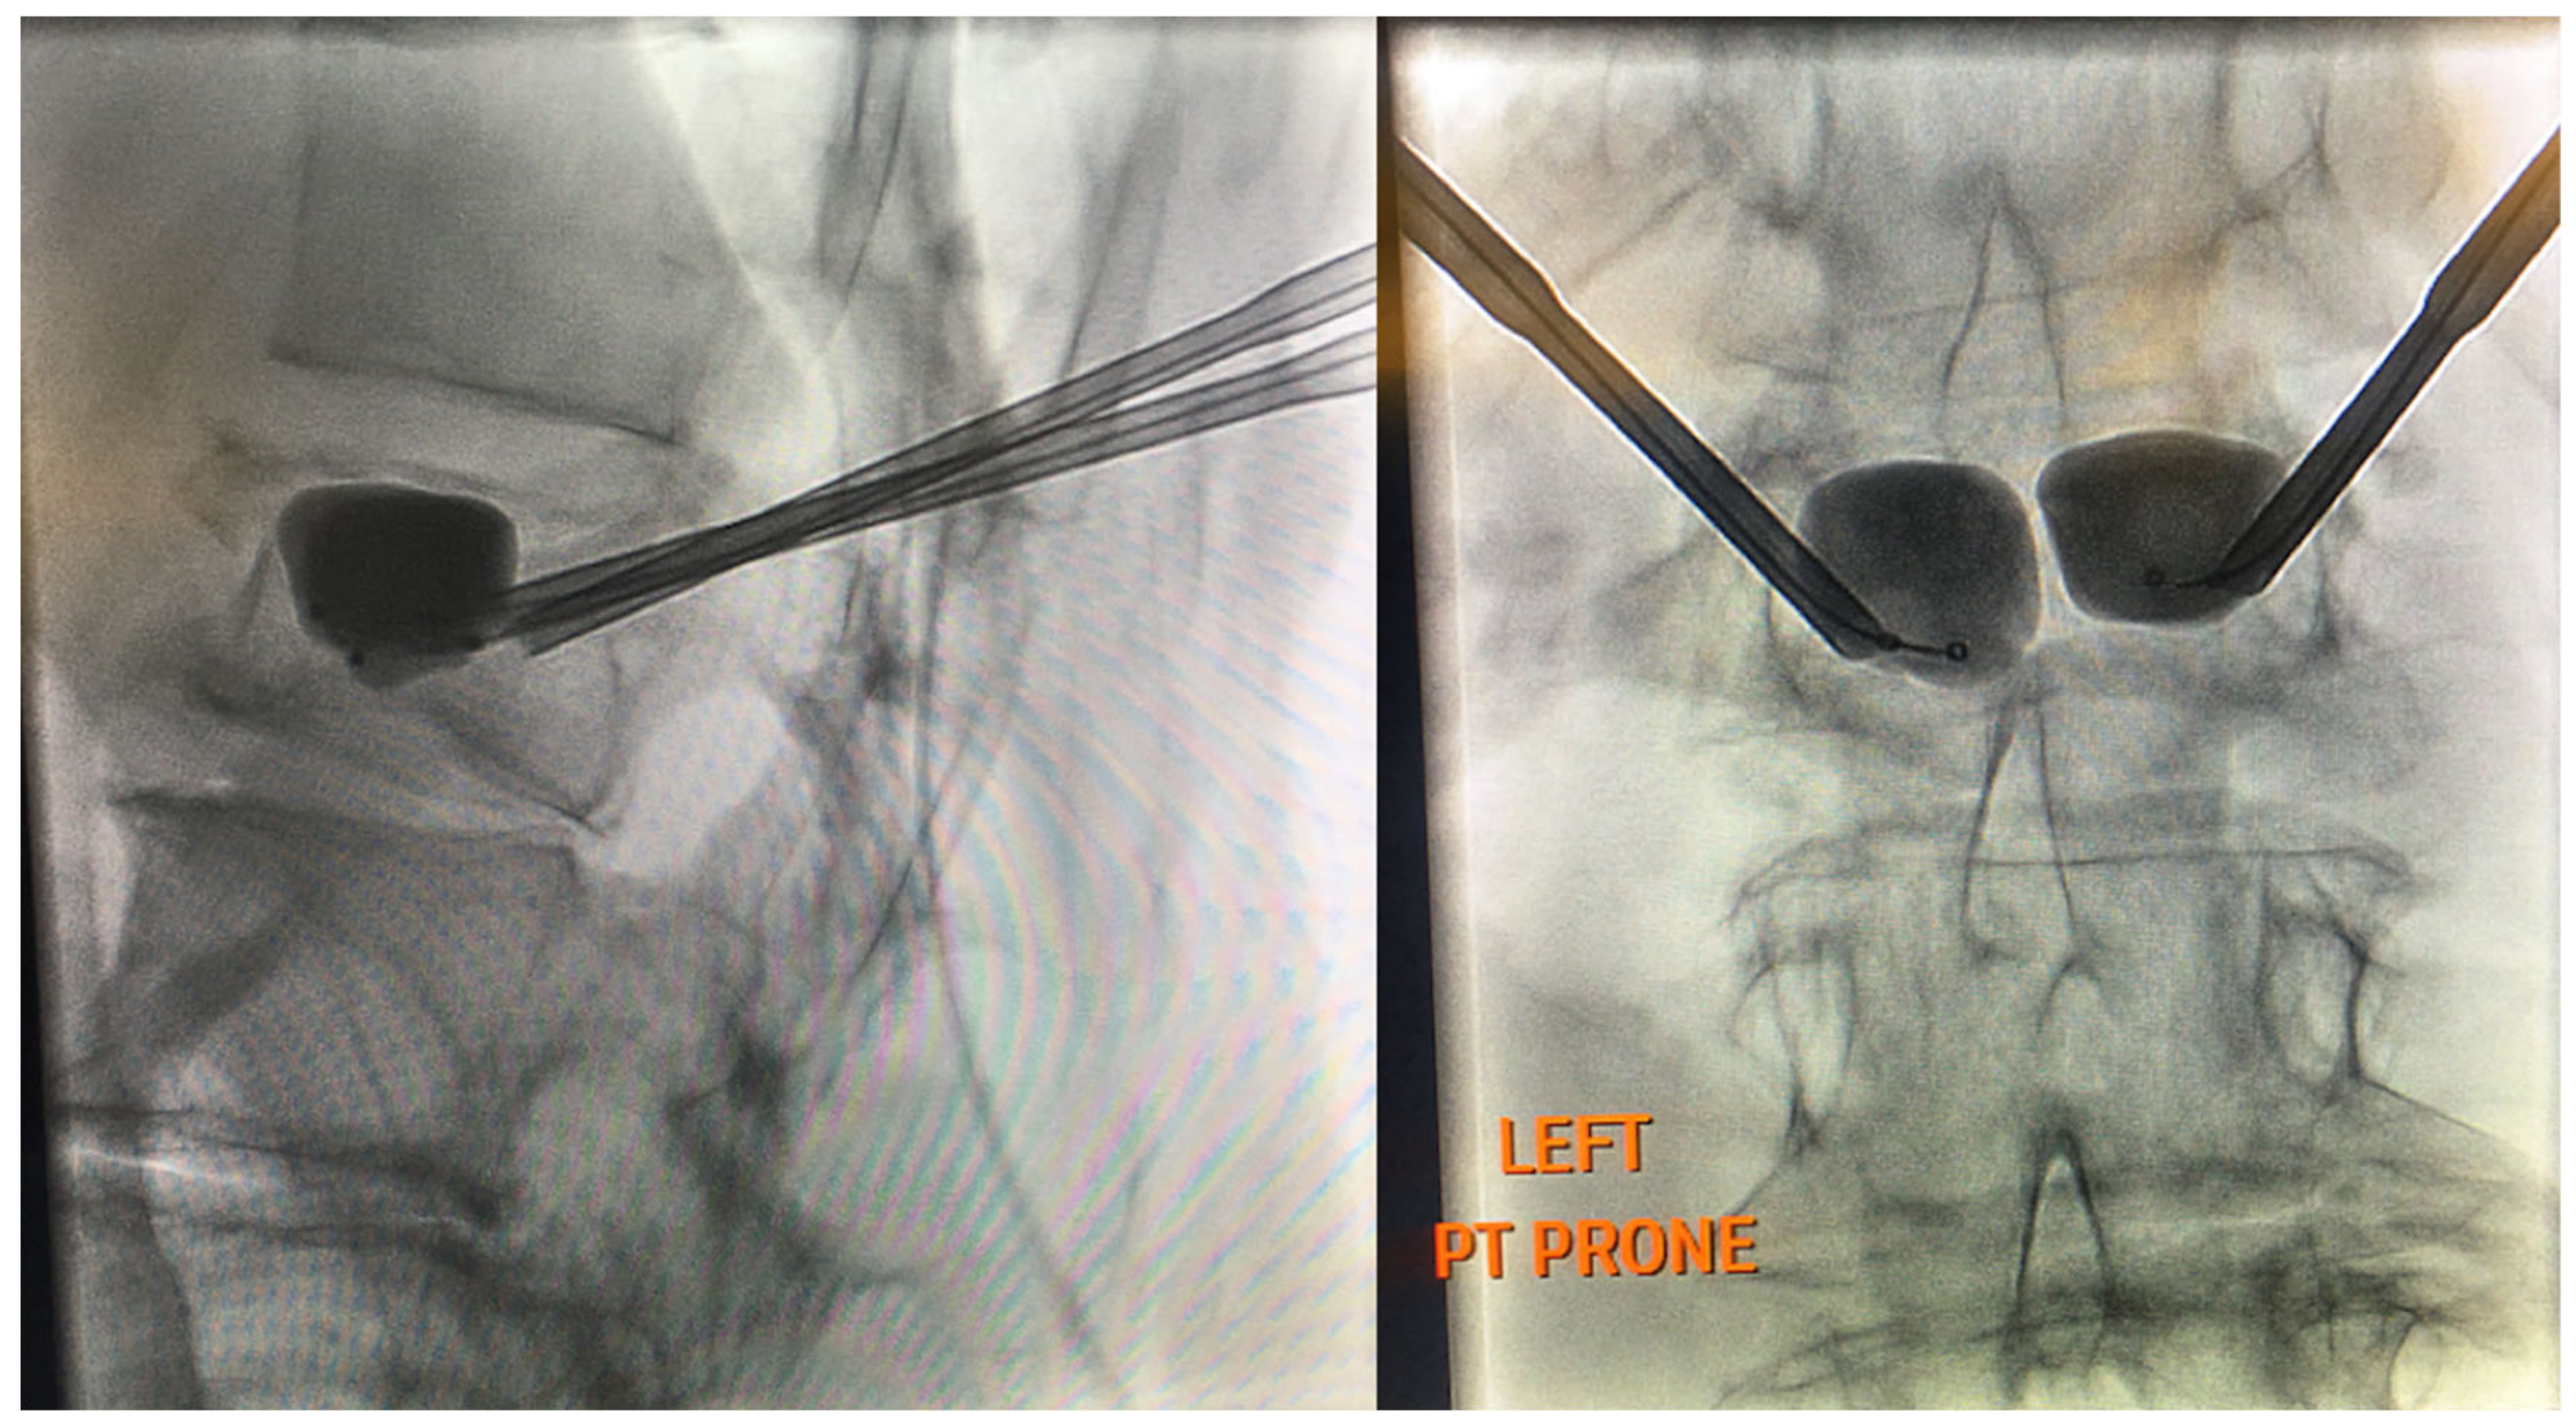

Vertebrogenic pain from endplate disruption is an etiology of chronic LBP that presents clinically different from other sources. Historically, the etiology of axial lumbar spine pain has been attributed to many anatomical structures, such as intervertebral disc degeneration, spinal canal narrowing, zygapophyseal joint pain, spinal ligaments hypertrophy, muscles and nerve root inflammation, etc. However, due to limited success with interventions targeting these structures, a recent shift in the vertebral pain treatment paradigm towards vertebral endplates has emerged. The basivertebral nerve (BVN) carries nociceptive input from damaged vertebral endplates related to inflammatory cytokines, substance p, and calcitonin gene-related peptide (CGRP), histologically confirmed with protein gene product (PGP) 9.5 positive staining under microscopy [111,112]. The BVN is a branch of the sinuvertebral nerve that enters the vertebral body and travels posterior-to-anterior to a bifurcation point about 50% into the vertebral body and divides cranially and caudally towards the endplates [113,114]. Basivertebral nerve ablation (BVNA) is a minimally invasive surgical treatment of vertebral pain performed similarly to vertebral augmentation and lumbar radiofrequency ablation, in the sense that it uses a transpedicular approach to the BVN bifurcation and delivers a high-frequency ablative lesion to interrupt nociceptive signaling from injured vertebral endplates (Figure 6) [115,116]. Vertebral endplates are highly vascularized structures that are particularly susceptible to post-traumatic degeneration, fissuring, intraosseous edema, and inflammatory changes [111,112,117,118,119]. These vertebral endplate changes have a specific phenotypic marker on MRI that directly correlates to vertebrogenic pain, known as Modic changes (MCs) type 1, type 2, and type 3 (Figure 7). Type 1 MCs manifest as the decreased signal intensity of fibrovascular intraosseous bone marrow edema on T1-weighted MRI sequences and as hyperintense or increased signal intensity on T2-weighted MRI sequences. Type 2 MCs represent fatty bone marrow infiltration and typically show an increased signal intensity in both T1 and T2 MRI sequence images in contrast to type 3 MCs that have decreased intensity in both MRI sequences [120,121,122]. Although MCs are radiological findings, their presence has been reported in up to 43% of subjects with spinal pain and is highly associated with this subset etiology [118,119,123,124]. Vertebrogenic pain from endplate damage presents clinically different than other etiologies of chronic LBP with reported painful episodes of greater duration and frequency and with significant functional impairment and disability compared to other etiologies. Pain tends to be axial and progressive in nature, aggravated by sitting, standing and spinal flexion and without radicular symptoms, numbness, tingling or motor weakness. This subset population tends to respond poorly to conservative treatment, epidural steroid injections, facet joint blocks and spinal surgery [112,118,119,121,123,124,125,126,127,128,129,130,131].

Figure 6.

Lateral and AP fluoroscopy views of curved stylet advancement towards the ideal location between the 25–40% midline, between the anterior and posterior vertebral walls.